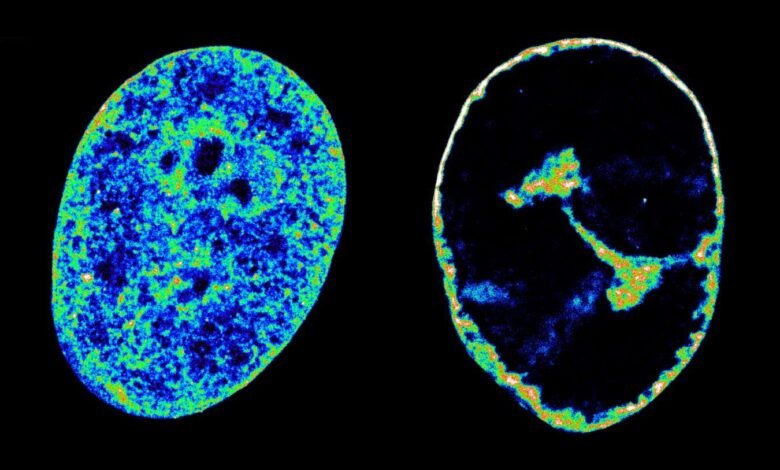

Human DNA in its natural state inside cells (left) compared with its state eight hours after being infected with the cold sore virus (right)

Esther Gonzalez Almela and Álvaro Castells García

But they also showed that this theft is what seems to cause the host DNA to coil up more tightly, making it shrink to 30 per cent of its pre-infection volume within eight hours of infection.